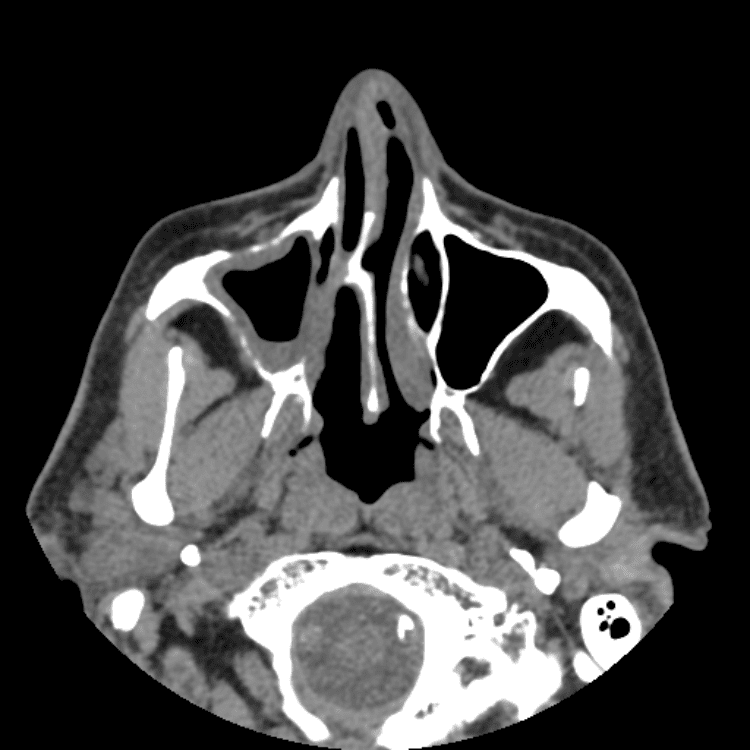

Head and Neck

Simulates call by including subtle or difficult cases and some normals.